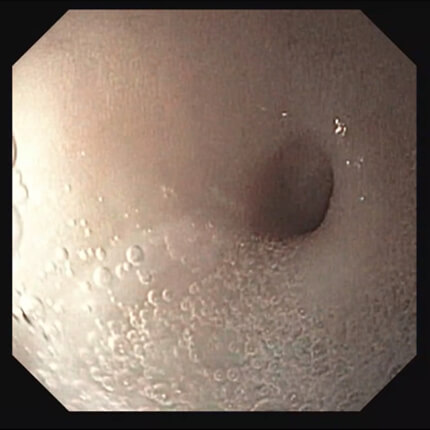

【胃体部】